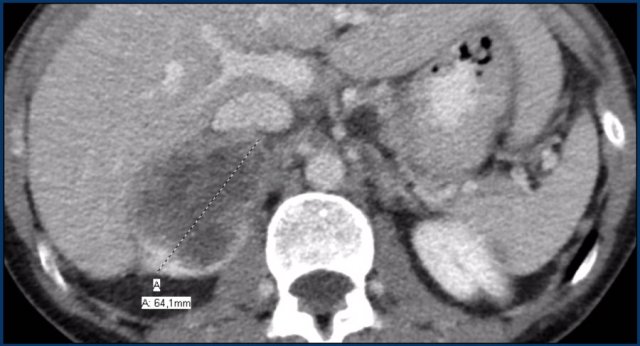

The images show bilateral adrenal incidentalomas found in a 64-year old patient scanned for analysis of an abdominal aneurysm.

The scan in the arterial phase shows bilateral lesions with a density of 50 HU.

On the non-enhanced CT performed a few days later, the density in both adrenal glands was less than 10 HU, proving these to be lipid-rich adenomas.